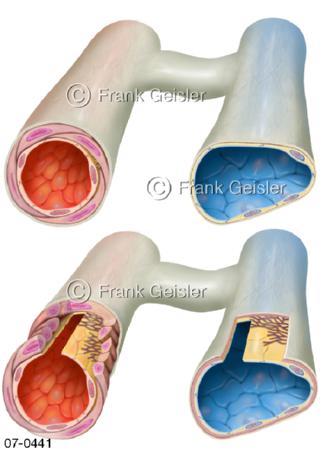

Bilder zu Herz, ein muskuläres Hohlorgan, das den menschlichen Körper durch rhythmische Kontraktionen mit Blut versorgt und dadurch die Durchblutung der Organe sichert, das Kreislaufsystem zeigt den Transport von arteriellem sowie venösem Blut durch das kardiovaskuläre System (Herz-Kreislauf-System), bestehend aus Blutgefäßen, Lymphgefäßen und dem Herz